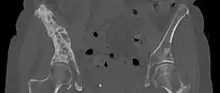

CT Scan

A CT scan can detect bone metastases before they present with symptoms in patients diagnosed with tumors that are high-risk for spread to the bone. Even sclerotic bone metastases are generally less radiodense than enostoses, and it has been suggested that bone metastasis should be the favored diagnosis between the two for bone lesions lower than a cutoff of 1060 Hounsfield units (HU).[10] If a biopsy is indicated, a CT scan is often used to localize the lesion before biopsy.[14]